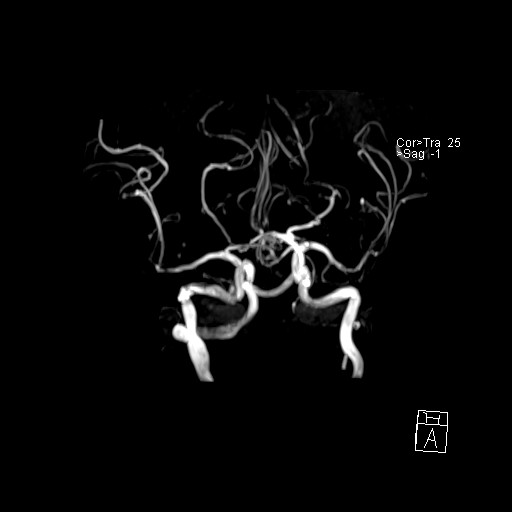

239716 - VILLANUEVA, WILLIAM A. - Number 4 |

|

239716 - VILLANUEVA, WILLIAM A. - Number 4 |